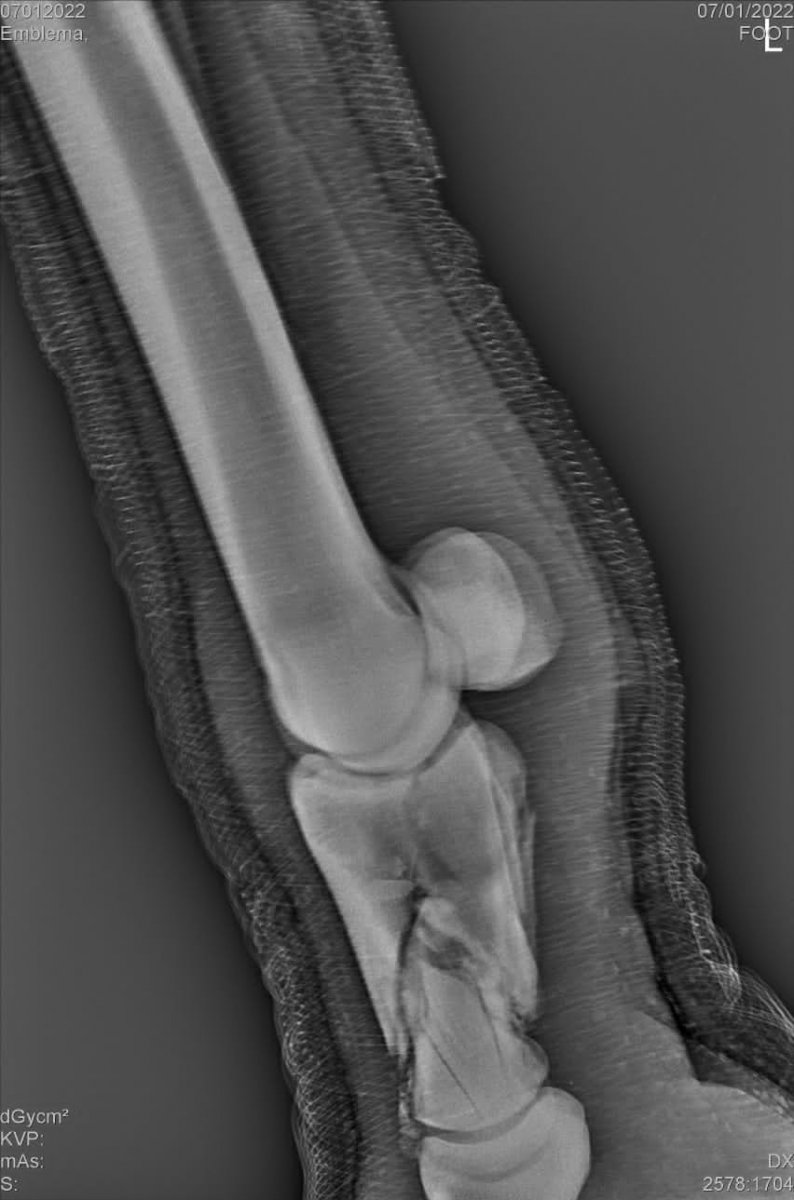

Вот такой был перелом и как он сросся через 6 месяцев

Полгода простоял в гипсе, меняли гипс через три месяца, потом ещё два месяца и один месяц в утягивающей повязке. Перелом был в июле, первый раз конь вышел из денника в декабре. Тяжелые были полгода, ему было тяжело самостоятельно вставать с гипсом, рекомендую положить резиновый пол в денник, чтобы ноги не скользили. Плюс он бился головой об поилку, перевесили ее в дальний угол денника. Очень сильно похудел, но в этот период много кормить нельзя, потому что лишний вес даёт нагрузку на здоровые ноги. Ел сено и гранулы без овса либо мэш. Обязательно кальций давать.

Вторая задняя нога сильно компенсировала поломанную, расчищать не могли толком, и там образовался небольшой ламинит в итоге. Перелом полностью сросся, но кость просела немного, поэтому ходит он не очень ровно. В остальном больше проблема со второй ногой, приходится делать ковку на зада, иначе сразу начинает хромать сильно.

После снятия гипса восстановился довольно быстро, месяца через три уже спокойно ходил сам